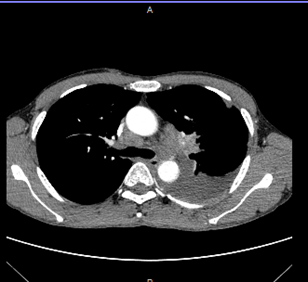

Hình ảnh CT ( 26/9/2022): Trước điều trị: Hình ảnh u thùy trên phổi trái, M màng phổi cùng bên. Xẹp thùy dưới phổi trái do tràn dịch. Hạch trung thất và hạch thượng đòn trái.

Hình ảnh CT ngực trước và sau điều trị:

Trước điều trị: Hình ảnh u thùy trên phổi trái, M màng phổi cùng bên. Xẹp thùy dưới phổi trái do tràn dịch. Hạch trung thất và hạch thượng đòn trái.

Sau điều trị: Đáp ứng gần hoàn toàn, hình ảnh u thùy trên phổi trái sau trị ( giảm KT nhiều so với trước điều trị). Màng phổi hai bên không có dịch.